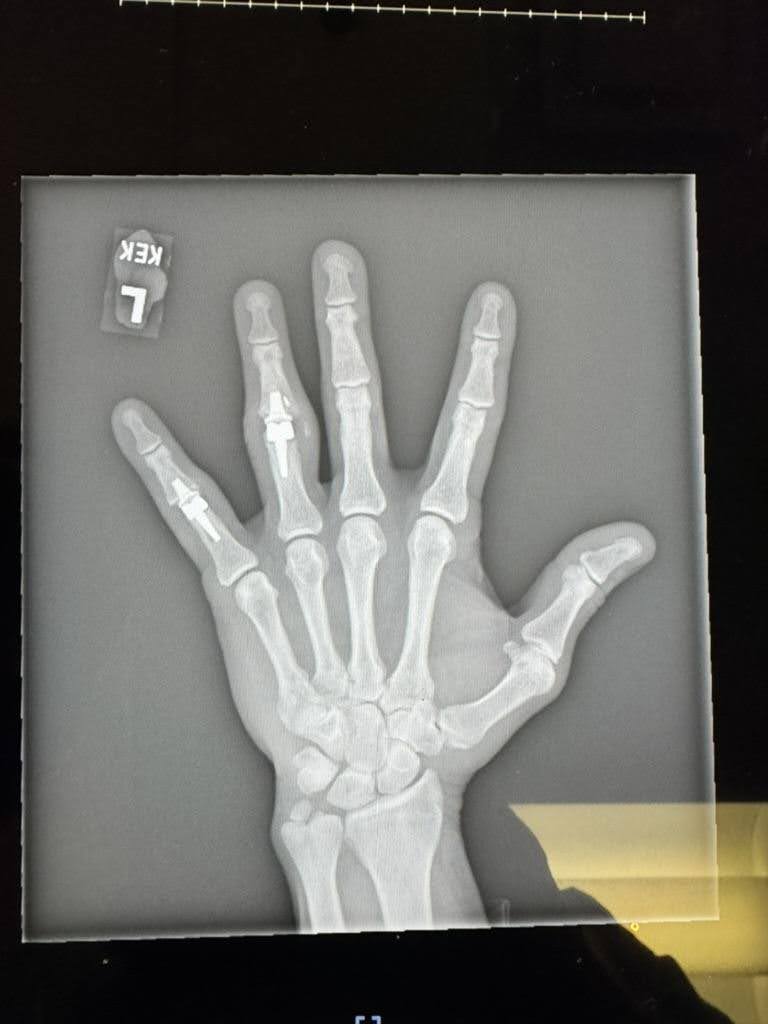

Finger Joint Arthritis and Joint Replacement Arthroplasty – Case 8

50 year old male with chronic post-traumatic arthritis with boutonniere deformities

The patient was reconstructed with Cobalt Chrome with Polyethylene cemented SR arthroplasty of ring and small finger PIP joints.

8 weeks post-operative result of PIP joint cemented SR arthroplasty of his left ring and small fingers.